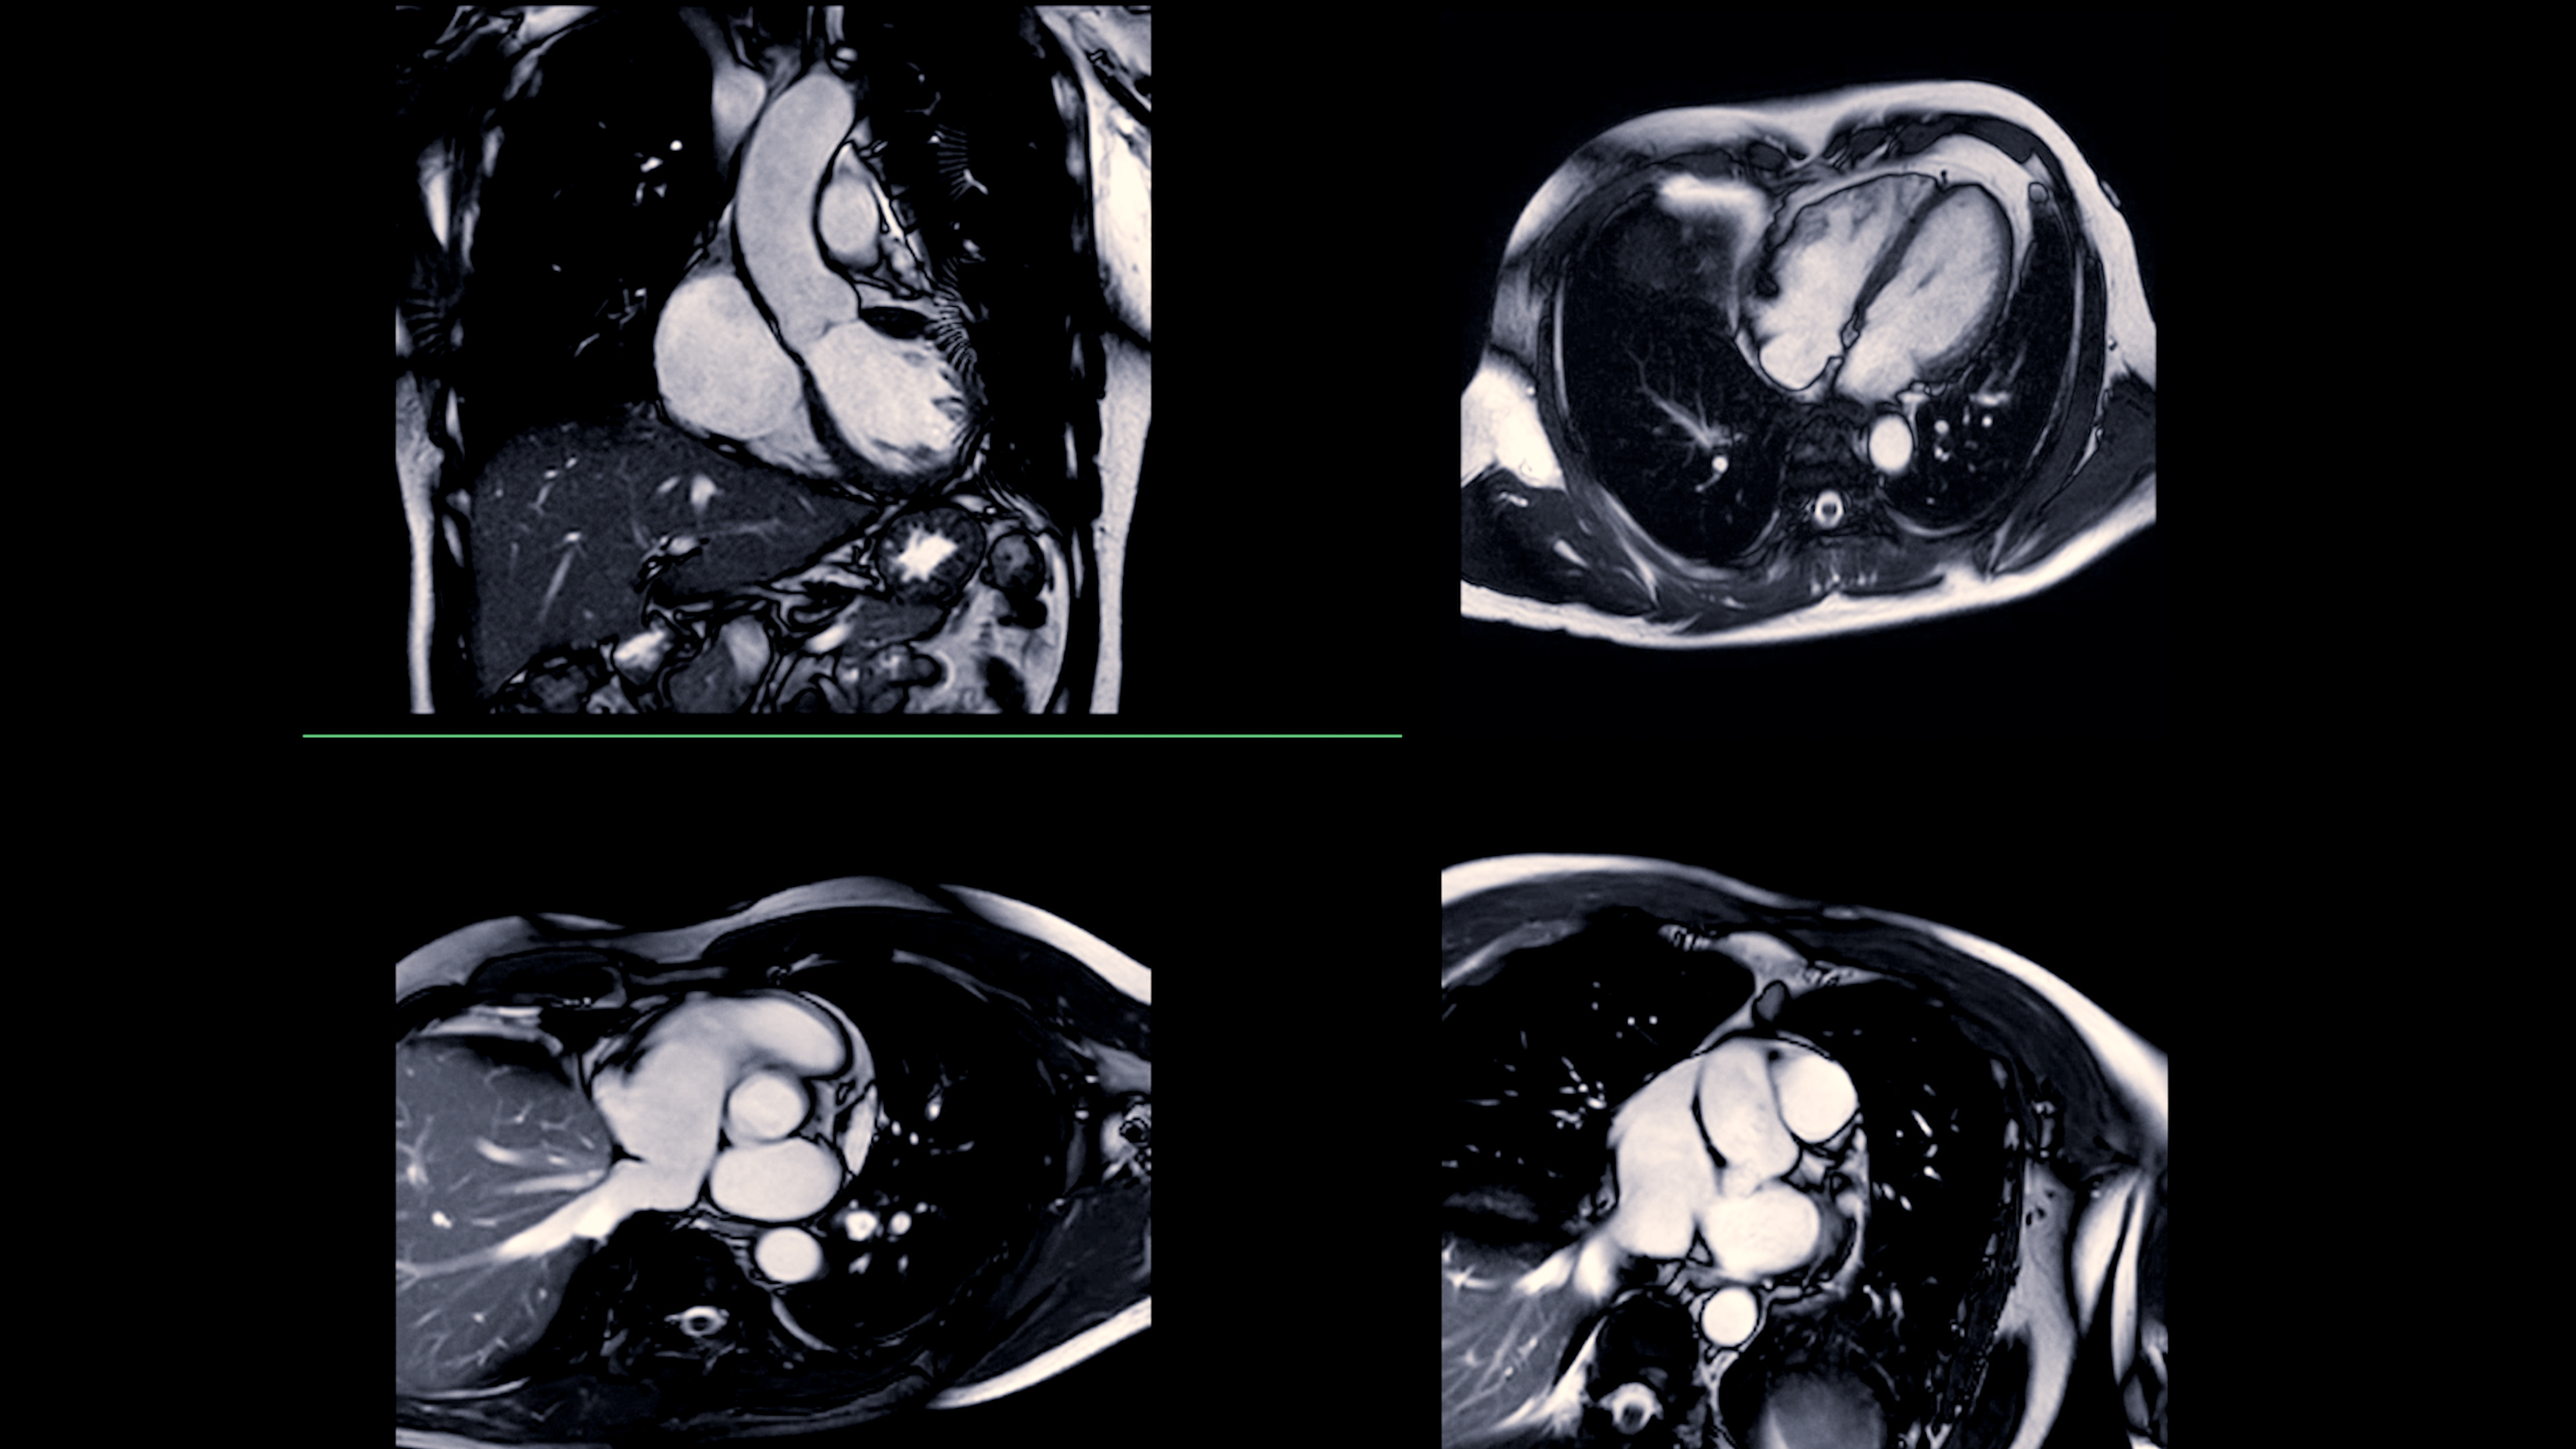

Diagnosoft v2.5 includes Diagnosoft Flow as an integrated component. The technology uses phase-contrast MRI to measure the velocity of blood flow through the heart and major vessels to identify problems in valve performance, arterial stenosis, and other anomalies.

Diagnosoft Plus v2.5 also features enhanced harmonic phase (HARP) measurement techniques to deliver enhanced images and analysis of regional myocardial strain and rotation.